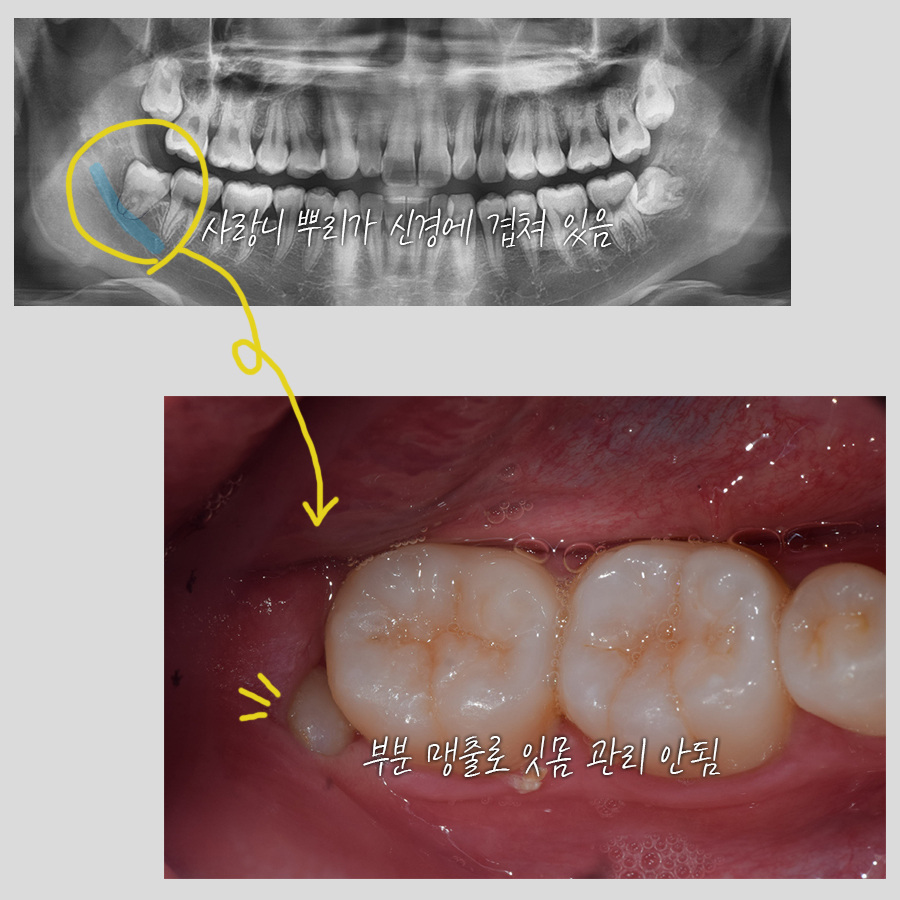

오늘 사랑니 발치 전문 치과에서 소개할 사례는

뿌리가 신경과 완전히 겹친 것과 멀리 떨어져 있는 것을 비교한 내용!

신경에 가까워 큰 병원 가래요.

라는 이유를 가지고 저흴 찾으셨던 분! 대학병원은 예약을 하려는 데도 한참을 기다려야 되고 어수선해 오히려 사랑니 발치 전문을 따로 알아보았다는 말씀에 참 감사했죠.

구강내 포토와 파노라마 엑스레이를 찍어서 보니 똑바로 선 매복치. 아주 조금만 잇몸을 뚫고 나온 상태였고 관리가 소홀했는지 그 사이로 음식물이 좀 끼어 있었죠. 이러니 염증이 생길 수 밖에~~

절개를 하고 앞 어금니에 걸리는 부분만 살짝 조각 낸 뒤 나머지를 톡~하고 뽑아냈어요. 어디로 갈지 고민을 했던 것이 민망할 정도로 순식간에 제거 된 수직 매복 사랑니! 모든 과정이 끝나고 데스크에서 소독 약속을 잡으실 때까지 계속 감탄을 연발하셔서 저흰 뿌듯했네요^^